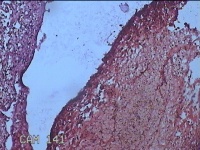

子宫腔内组织

性别

女

年龄

39岁

临床诊断

早期人工流产

一般病史

停经36天。

标本名称

大体所见

灰白暗红色不规则碎组织3x2.5x1.3cm一堆,未发现明显的绒毛样组织。

不具诊断价值。

在切片质量方面还需要加把劲。